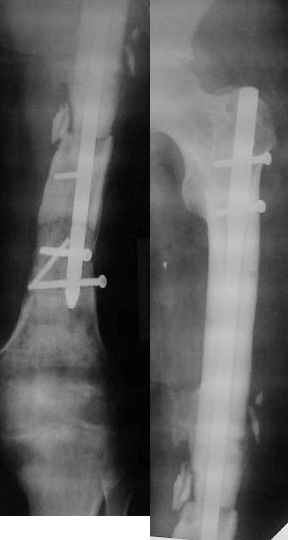

[Ortho] Ложный сустав в/3 плечевой кости!

Неудачный остеосинтез пластиной: поломка винтов, миграция фиксатора.

После удаления пластины сформировался гипопластический ложный сустав

нижней трети бедренной кости, укорочение н/к 5 см. Выполнялся

дистакционный остеосинтез аппратом Илизарова на штифте. Зона ложного

сустава "не открывалась". Через 10 месяцев, когда даже  регенерат

полностью перестроился, консолидации в зоне ложного сустава не

наступило, несмотря на стабильную фиксацию и постоянную

компрессию(штифт+аппрата на 4 кольцах).